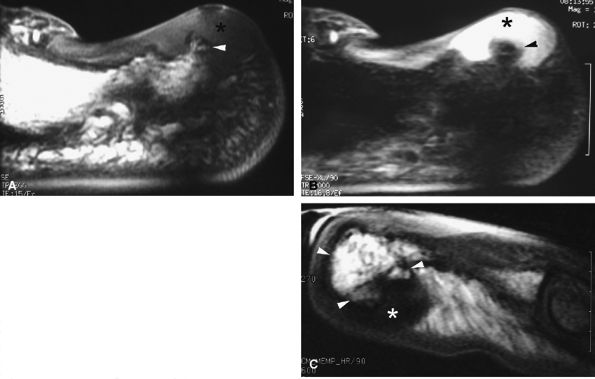

seen with synovial sarcomas. Bone and joint invasion is possible.168 Ultrasonography shows a nonspecific solid mass with a variable color Doppler signal. MR images are specific, depicting a well-defined mass with hemosiderin deposits. Typical signal void artifacts are seen on all sequences, particularly on gradient-echo images, and a more heterogeneous and predominantly low signal is found on T2-weighted images.162,166,169 The lesion typically enhances after intravenous injection of gadolinium (Fig. 11.74). The tendon sheath of the flexor digitorum tendons is usually partially or totally enveloped; the extensor tendons are less commonly involved. Some lesions may be more aggressive, and diffuse lesions are seen in multiple locations with invasion of both the flexor and extensor tendons (Fig. 11.75).170

![]() |

FIGURE 11.73 ● Giant cell tumor of the tendon sheath. Lateral view radiograph shows a large mass of the palmar soft tissue (asterisk) and bone pressure erosion (arrows).

FIGURE 11.74 ● Giant cell tumor of the tendon sheath. Sagittal T2-weighted image (A) and post-contrast T1-weighted image (B) show a palmar mass (arrows) close to the sheath of the flexor tendons with predominant low signal (arrowhead) on the T2-weighted image and strong enhancement following contrast administration.

FIGURE 11.75 ● Aggressive giant cell tumor of the tendon sheath. Sagittal post-contrast 3D gradient-echo (A) and axial T1-weighted (B) images depicting a multinodular tumor invading the flexor and extensor tendons as well as the head of the phalanx (arrow).